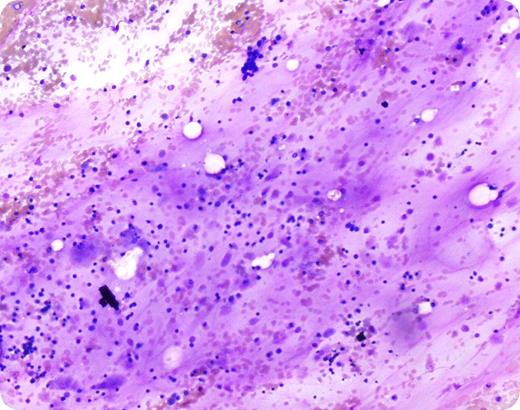

A 25-year-old white female with a history of an eating disorder presented with pancytopenia. Hematopoietic elements including erythroid precursors and megakaryocytes can be recognized in addition to a few fat cells. The amorphous material represents deposit of hyaluronic acid with gelatinous transformation of the marrow. (Wright-Giemsa stain, 10× magnification)